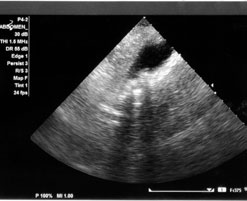

A scan is necessary to confirm gallstones. Most commonly, an ultrasound is performed. Stones may also be detected on CT scan or MRI of the abdomen. In addition, your doctor will also do a blood test to rule out any obstruction of the bile ducts.